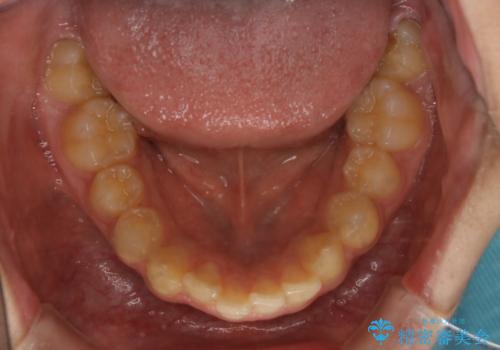

非抜歯で劇的に出っ歯を改善!インビザラインとカリエールの組み合わせ治療

- 患者様、出っ歯のお悩みで来院されました。

骨格の分析を行ったところ上顎も出てはいるのですが、下顎が引っ込んでいる状態であるということがわかりました。

よって上顎の歯を抜いて治療をするのではなく、カリエールという器具を使用して下顎を前に引っ張り出しながら上顎を引っ込めるという治療を行うことにしました。